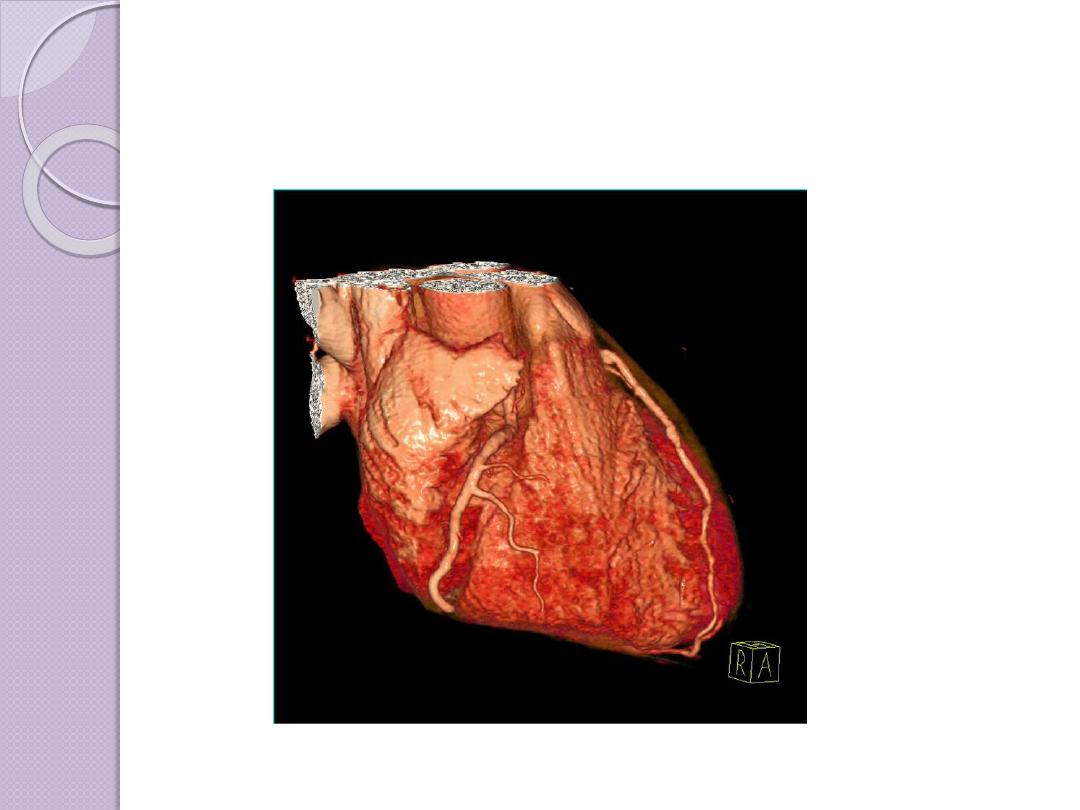

ADVANCES OF CT

Faster CT machines, due to multidetector

capabilities, have made imaging of

the

and

very

practical in a number of clinical

settings.The faster capability has allowed

the imaging of the heart with minimal

involuntary motion, which creates

3D

RECONSTRUCTION

Multiplanar

reconstruction the

simplest method of

reconstruction. A

volume is built by

stacking the axial slices

Advantages of CT scan

CT is very good for imaging bony

structures and calcifications.

Good soft tissue and spatial resolution .

Short examination time ( suitable for

pediatric and some emergencies )

Suitable for Coronary and cardiac

examination ( advance multi

detector CT scan )